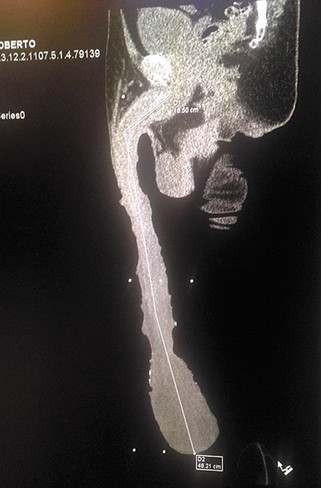

“De acuerdo con la tomografía en tercera dimensión sí es su cuerpo; se descarta una prótesis y sabemos que el cuerpo principal mide unos 16 centímetros y el resto, para llegar a 48.2, es un exceso extraordinario de piel. Sólo un urólogo y seguramente otros exámenes podrán determinar al 100 por ciento”.